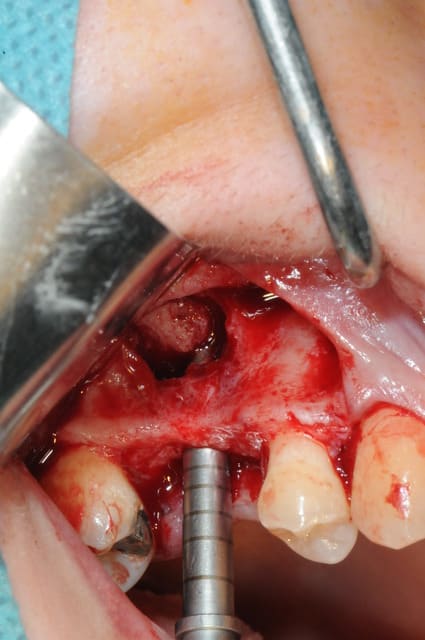

le sujet tombe à pic!

je viens de faire un sinus lift ce matin;

- 3 à 4 mm de hauteur sous sinusienne

- des cloisons de refend partout

- comblement avec du Vital Os

- un implant Axiom D4 L 10

comme je n'avais pas le temps de faire des photos la dernière fois et que j'en étais frustré, je me suis un peu lâcher aujourd'hui...

les premières photos, c'était ouverture par voie latérale

- forage et transperçage de la crête sans aller trop loin...

- essayage pilier pour parallélisme

- forage à 3mm

- visualisation de la hauteur sous la membrane de Schneider

- utilisation d'un ostéotome diamètre 3.4 puis 3.8

(sous dimensionnement de diamètre par rapport à l'implant prévu :4mm)